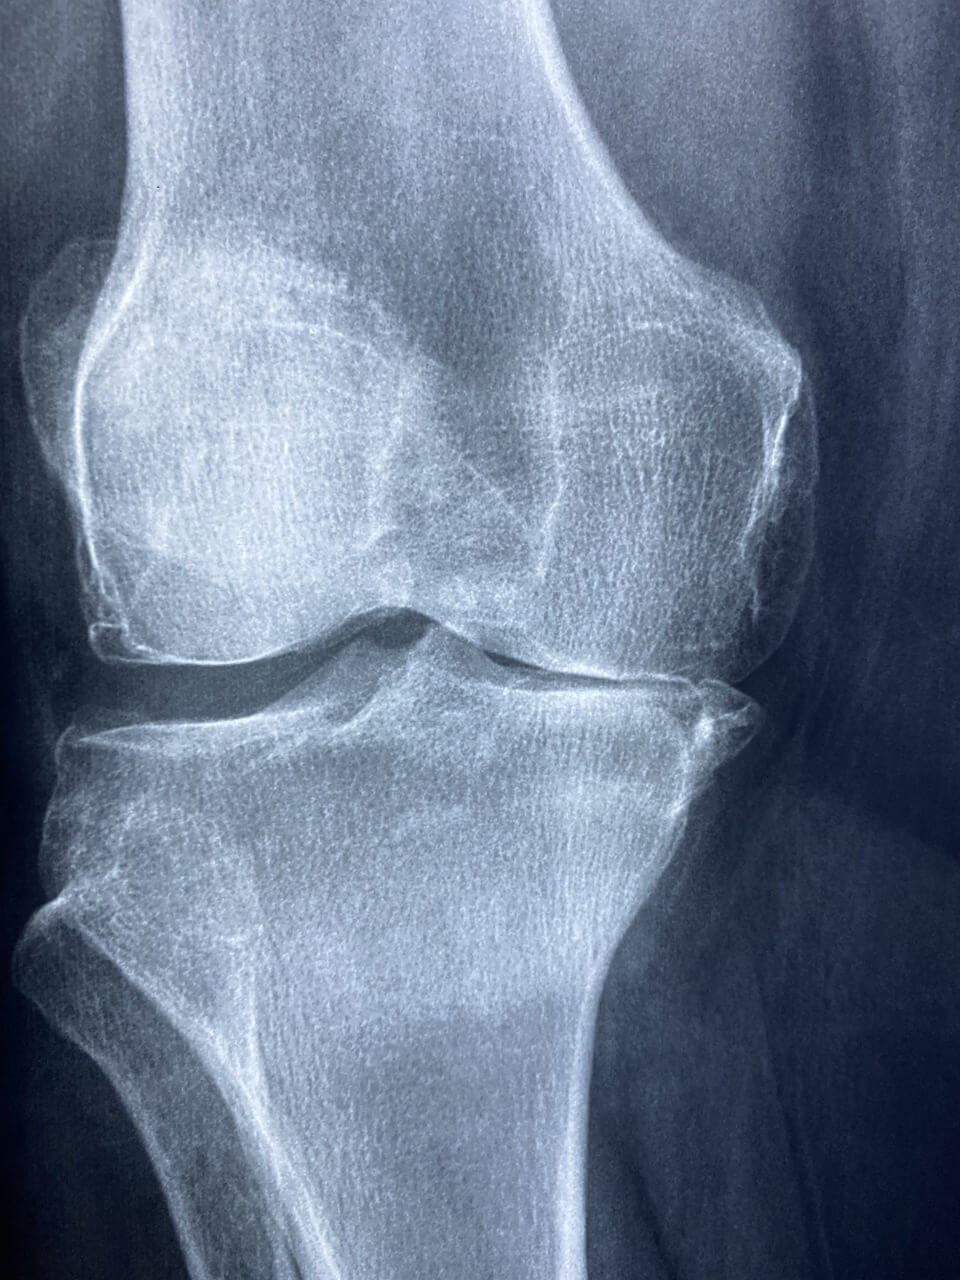

나이가 들어감에 따라 연골의 악화는 종종 관절 통증과 불편함을 유발하여 이동성을 방해하고 전반적인 삶의 질에 영향을 미칠 수 있습니다. 연골의 필수 구성 요소인 콘드로이틴은 뼈 사이의 쿠션 역할을 하여 신체 활동 중 충격을 흡수하는 데 도움을 줍니다.

콘드로이틴은 관절의 뼈 사이에 쿠션을 제공하는 유연한 조직인 연골의 중요한 구성 요소입니다. 나이가 들어감에 따라 우리 몸의 콘드로이틴 양이 감소하여 관절 통증과 뻣뻣함을 유발할 수 있습니다. 콘드로이틴을 보충하면 연골 조직의 유지 및 복구를 지원하여 관절 건강을 개선하는 데 도움이 될 수 있습니다.